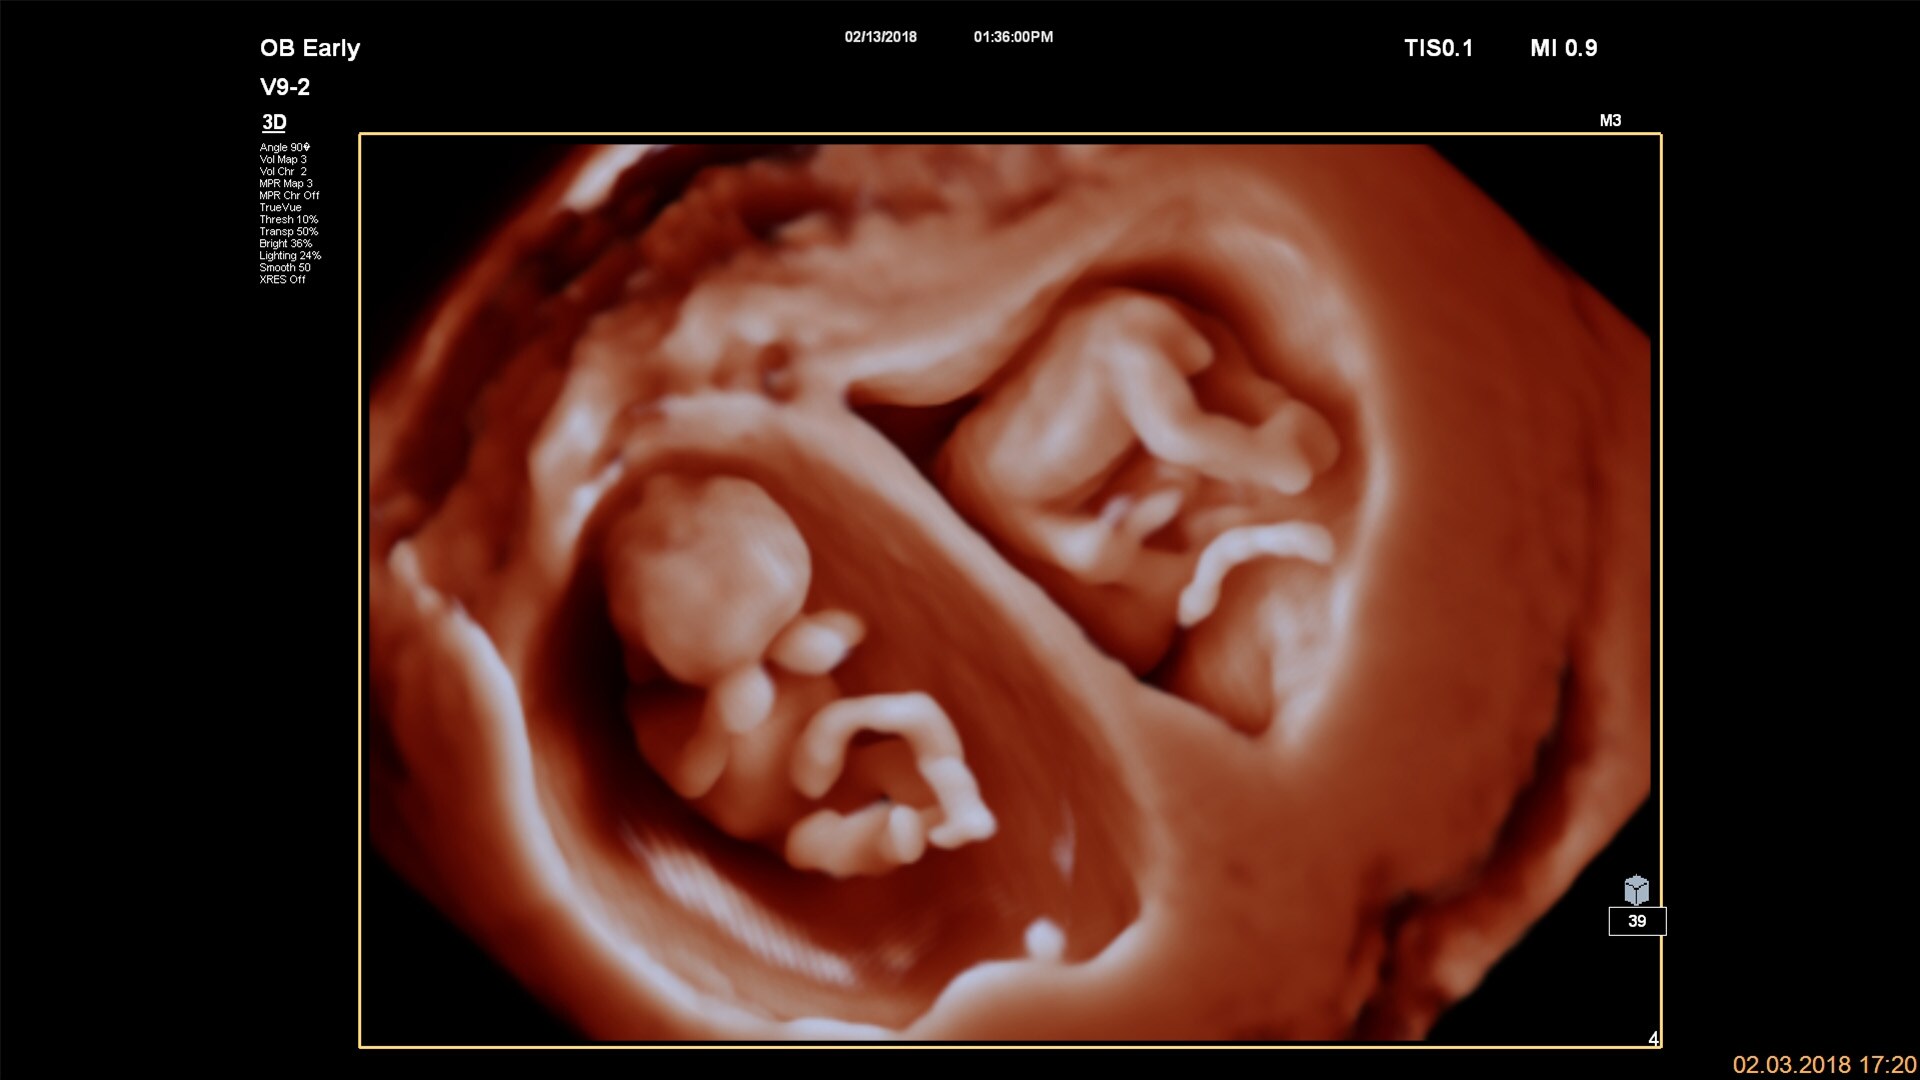

Noul traductor volumetric V9-2,

foarte silențios și cu greutate redusă, vă oferă imagini 2D și 3D/4D de o calitate excepțională

Tehnologia TrueVue şi TouchVue

Funcţia Philips TrueVue cu sursă virtuală de lumină reprezintă o metodă brevetată de imagistică ultrasonografică în tehnologia 3D, permiţând obţinerea de proiecţii tridimensionale realiste. Operatorul aparatului poate mişca în orice mod sursa de lumină, în cadrul volumului imaginii 3D. Folosind interfaţa interactivă TouchVue, utilizatorii ecografului pot, cu ajutorul panoului tactil, să controleze atât rotirea volumului, cât şi amplasarea sursei interne de lumină direct pe imaginea 3D obţinută cu ajutorul funcţiei TrueVue.

Traductor convex volumetric V9-2